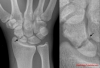

Günlük hayatımızda ya da spor aktiviteleri sırasında düşme, sert top gelmesi gibi durumlar el bileğinde ağrı, şişlik ve hareket kısıtlılığı oluşturabilir. İlk bakışta hasta tarafından önemsenmeyen bu durum şikâyetlerin devam etmesi üzerine doktora başvurmayı gerektirir. İlk günlerde şikâyetler hastayı doktora götürecek kadar rahatsız edici olmasa bile 1 haftayı geçen şikâyetler olayın basit bir burkulmadan daha ciddi bir durum olabileceği konusunda kişiyi şüphelendirmelidir. Özellikle avuç içi yere basar şekilde düşmelerde skafoid kemik kırığı oluşabilmektedir. Düşmenin ilk gününde çekilen röntgen görüntülerinde kırık tespit edilemeyebilir. Bu şekilde kırığın tespit edilememesi tedavinin gecikmesine, kırığın yanlış kaynamasına ya da kaynamamasına sebep olabilir. Bu sebeple ilk doktor başvurunuzda tanı konmasa bile şikâyetlerin devam etmesi durumunda mutlaka tekrar kontrol gereklidir.

El bilek travması sonrası ilk 3 hafta içinde tanı konulan kırıklar erken evre olarak değerlendirilebilir. Bu dönemde eğer kırık skafoid kemiğin anatomik yapısını bozmamışsa el bilek kemiklerinin dizilimi normal ise 8-12 hafta alçı ile takip sonrasında kırığın kaynama olasılığı %80 in üzerindedir. Bu dönemde mesleki yada farklı sebeplerden dolayı alçı uygulanmasını tolere edemeyen hastalarda, cilt kesisi yapılmadan skopi ( anlık röntgen çekebilen cihaz) kontrolü altında kırık özel olarak imal edilmiş vidalar yardımıyla tespit edilebilir. Bu tedavi sonrasında hastaya alçı kullanmadan kontrollü el bilek hareketi başlanabilir.